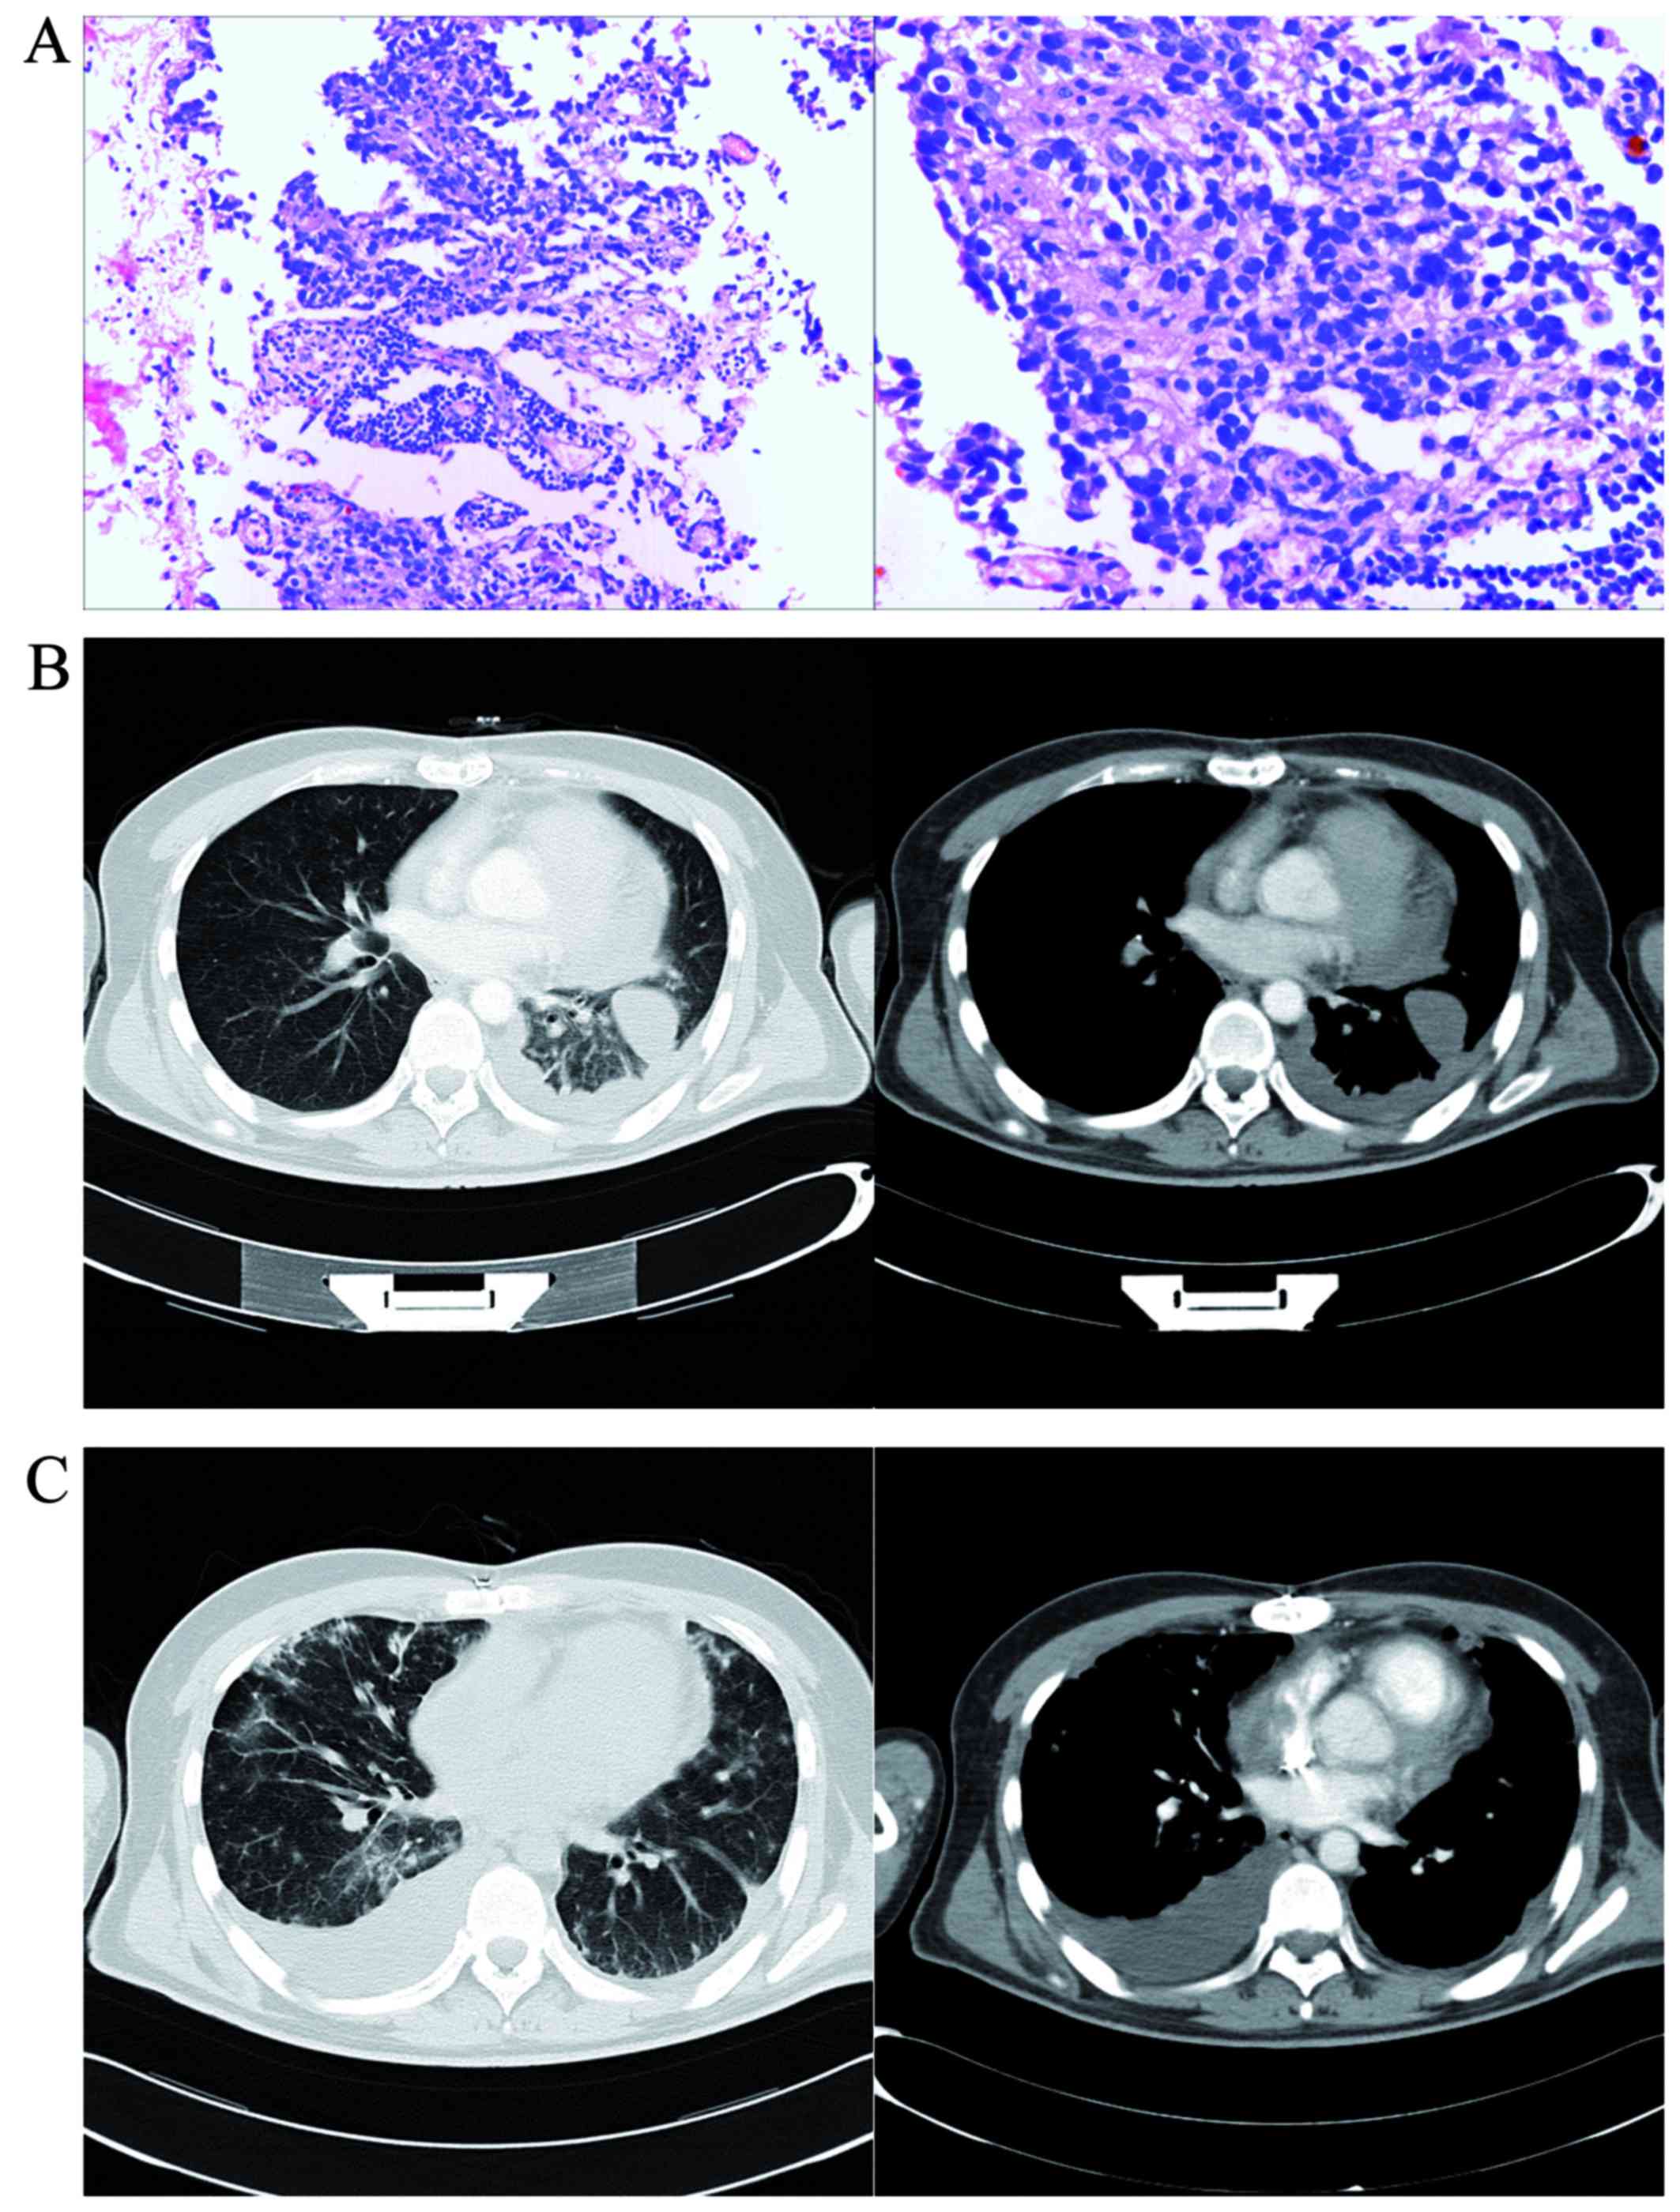

In May 2010, a 28-year-old man was admitted to the Nanjing First Hospital due to progressive left-sided chest pain and breathlessness for 4 months, which had worsened over the last 1 h. The patient had a 10-year history of smoking (1 pack/day). There was no history of tuberculosis or asbestos exposure. Two months prior to admission, the patient had been hospitalized with the same symptoms in another hospital. Physical examination, chest radiography, computed tomography (CT) and enhanced CT revealed widening of the myocardial boundary, concurrent large pericardial effusion and little-to-moderate pleural effusion (Fig. 1B). A total of 1,800 ml of pericardial fluid were evacuated. Cytological examination of the pericardial fluid only found reactive mesothelial cells, without acid-fast bacilli or tumor cells. Echocardiography revealed thickening of the free wall of the right ventricle (RV), with adhesions to the adjacent pericardium and uneven thickening of the right atrium (RA) to 0.8–1.4 cm. The thickened pericardium near the output of the RV has also restricting myocardial motion. A liquid anechoic area was detected in the pericardial cavity and pericarditis was highly suspected (Fig. 1A). Experimental antituberculosis treatment was refused when the Mantoux test was found to be strongly positive. The patient was referred to our hospital due to worsening shortness of breath and was tentatively treated with antituberculotic agents (isoniazid and rifampin), with a poor therapeutic effect and increasing volume of the pericardial effusion. 18F-FDG imaging was performed to rule out malignancy; it revealed highly increased uptake of 18F-FDG in the RA, the pericardium adjacent to the RV and RA (Fig. 2B and C, arrows), and mildly increased uptake along the inner thoracic wall (Fig. 2B, arrows). Ring-shaped radioactivity aggregation and bone destruction in the sacrum were visualized on 18F-FDG imaging (Fig. 2D and E, arrow) and 99mTc-methyl diphosphonate (MDP) whole-body scan (Fig. 2A, arrow). PMPM with RA infiltration and bone metastasis was highly suspected. An incisional pericardial biopsy was performed and pathological examination of the samples obtained by biopsy confirmed the diagnosis of PMPM with atrial infiltration (Fig. 3A) (cytokeratin5/6+, D2-40+, calretinin+, carcinoembryonic antigen−, thyroid transcription factor 1−). Following surgery, a doublet chemotherapy regimen (pemetrexed 500 mg/m2 + cisplatin 75 mg/m2 were administered on the first day of each 3-week cycle, for a total of six cycles) was introduced immediately after definitive diagnosis. During follow-up, CT imaging revealed little pericardial effusion at 4 months postoperatively (Fig. 3B), but lung metastasis and large pleural effusion were observed 1 year after the operation (Fig. 3C). The patient survived for >1.5 years after the diagnosis and succumbed to severe pericardial effusion and cardiac tamponade in September 2012.

Figure 3.

Pathology of pericardium and computed tomography (CT) images at 4 months and 1 year after surgical resection. (A) Tissue from the pericardium and adjacent atrium strained with hematoxylin and eosin staining (original magnification: left panel, ×50; and right panel, ×100) revealed diffuse infiltration of the pericardium by epithelioid cells in papillary arrangements. The tumor cells were characterized by abundant cytoplasm, prominent nuclei and cytoplasmic vacuoles. (B) No pericardial effusion and little pleural effusion were observed at 4 months after the operation on contrast-enhanced CT (left panel, lung window; and right panel, mediastinal window). (C) Multiple lung metastases and a large pleural effusion were found at 1 year postoperatively (left panel, lung window; and right panel, mediastinal window).